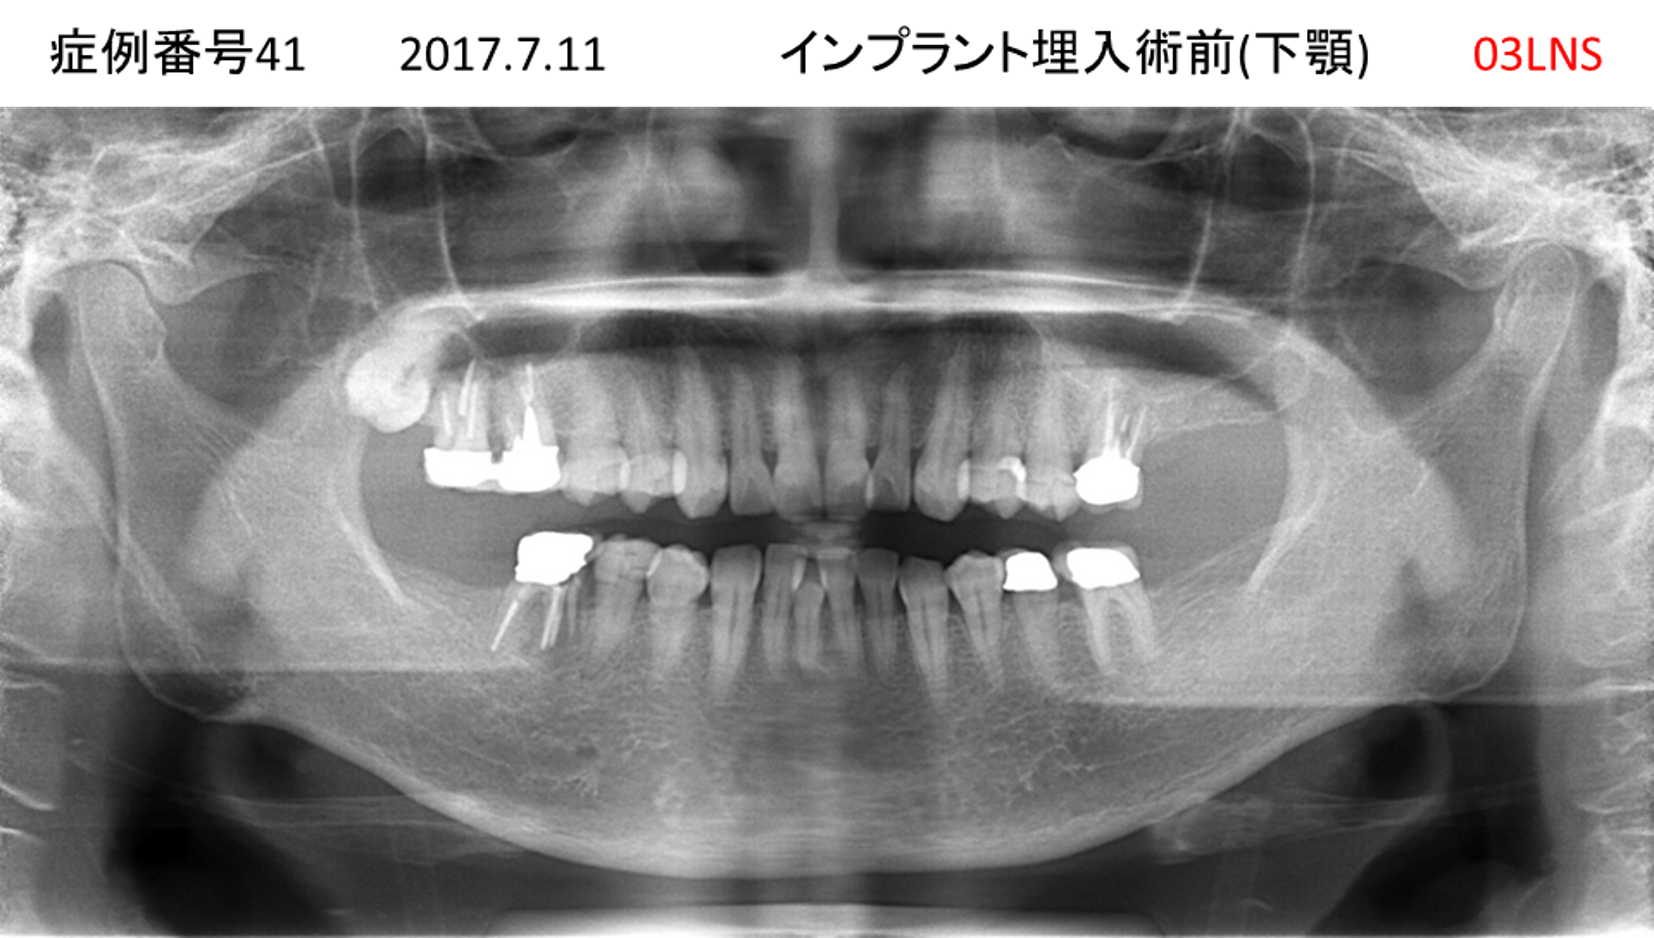

奥歯で噛めない患者様のインプラント症例

| 治療名称 |

インプラント |

| 治療費用 |

365万円+税 |

| 治療期間 |

5か月 |

| 患者さんの症状(主訴) |

奥歯で噛めない。上の前歯が揺れてきた。 |

| 治療内容 |

抜歯即時インプラント |

| 治療結果 |

食事に困らない。見た目がとても良くなった。 |

| 治療の注意点(リスク/副作用) |

インプラントが壊れたら再治療が必要 |